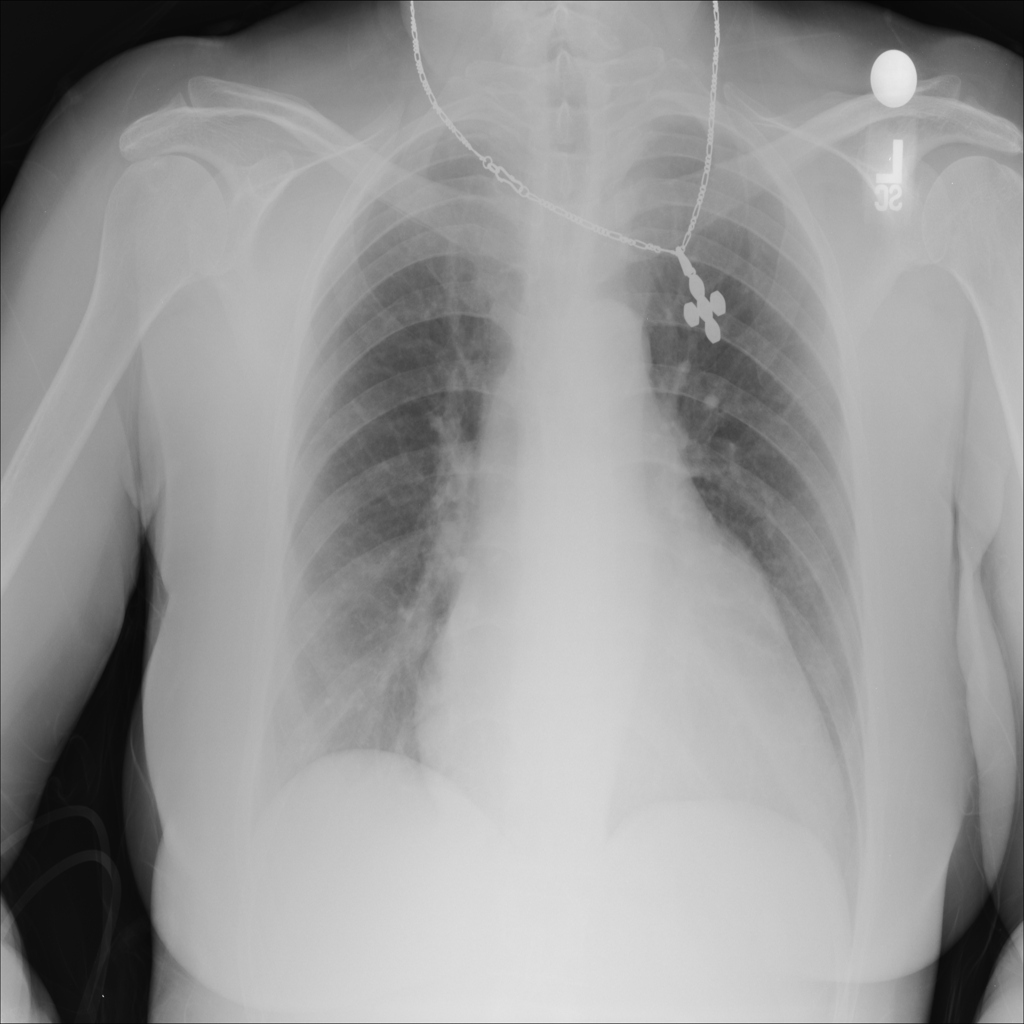

Showing up to 90 reference images for Cardiomegaly.

PAT-AE5C · IMG-000Cardiomegaly

PAT-AE5C · IMG-000

PA